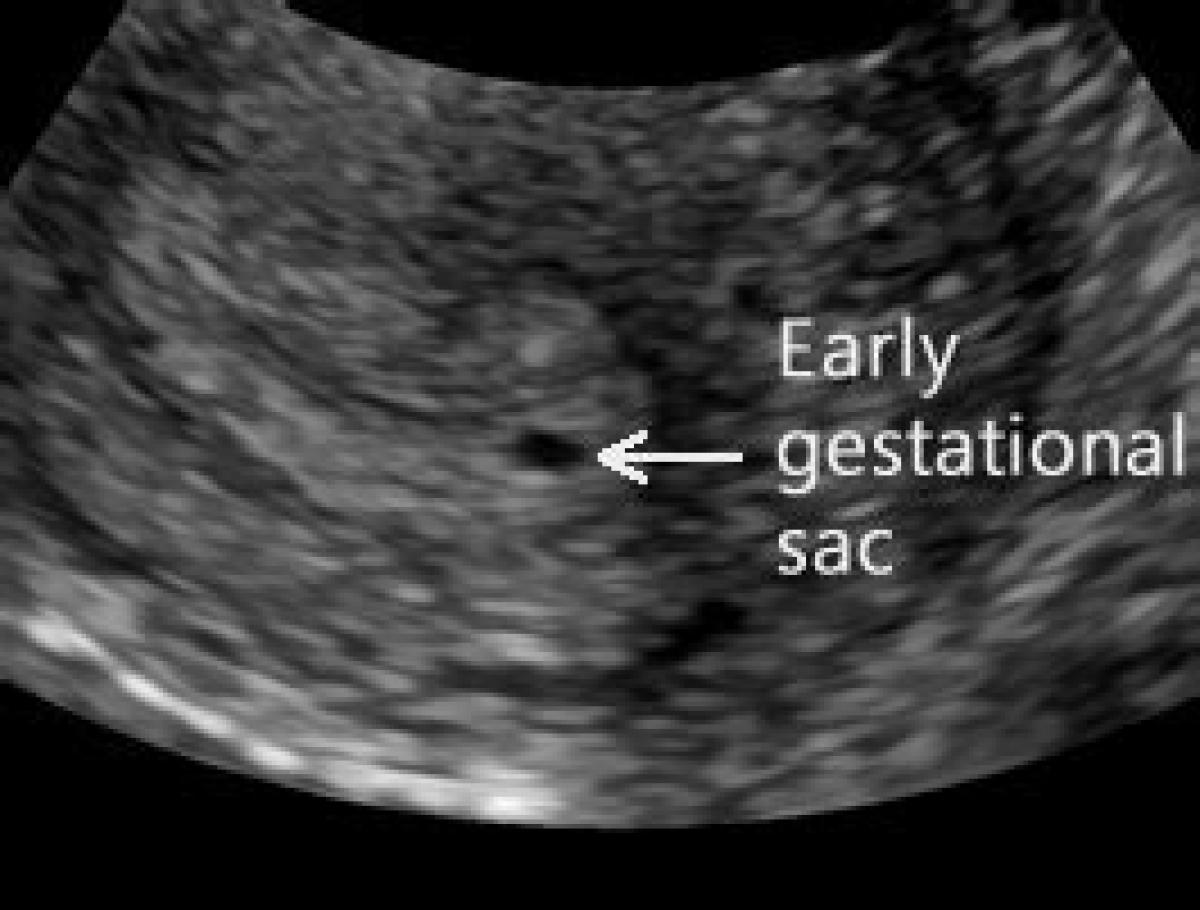

مخفف GS Gestational Sac این اصطلاح در سونوگرافی بارداری به معنی کیسه حاملگی (GS) است.مشاهده نسخه کامل